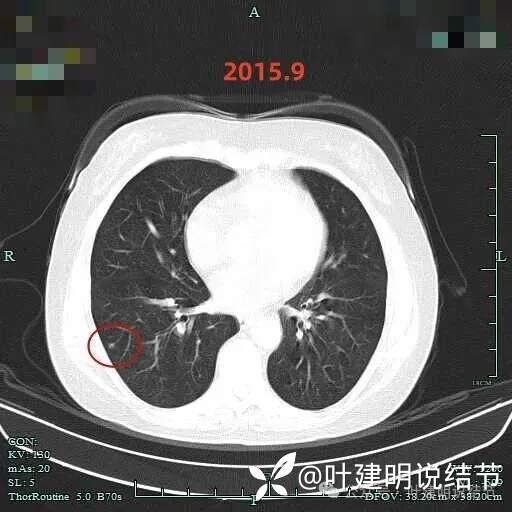

到了2015年9月,结节仍在,且有微小血管进入的样子,大小仍小,密度不太纯,轮廓较清。